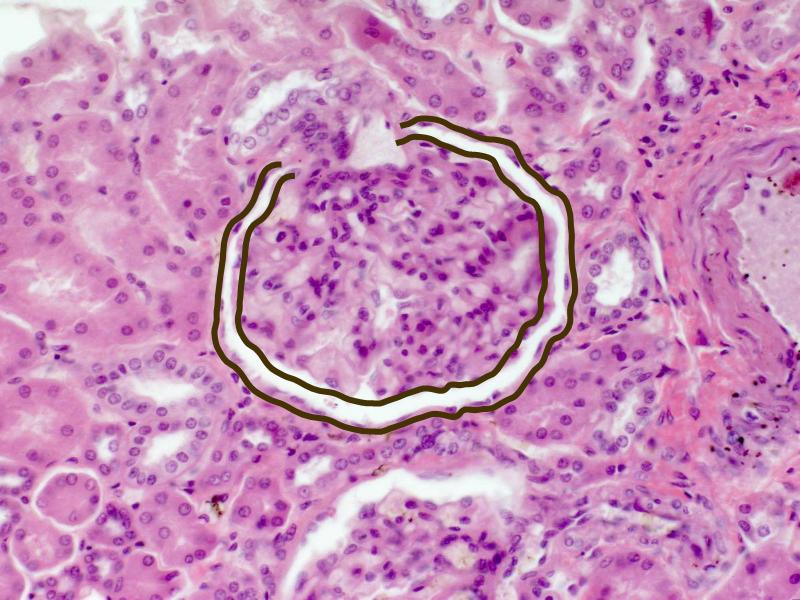

- The renal corpuscle

- Complete the drawings for each slide in the practical workbook.